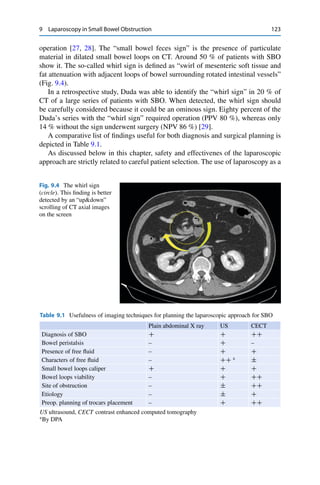

• 227.

218 C. Rossiet al. – Enhancing soft tissue narrowing the colonic lumen – “Shoulder sign,” central necrosis in a large obstructive mass – Pericolonic fat infiltration (differential diagnosis with diverticulitis) – Lymph nodes larger than 1 cm Sigmoid Volvulus – “Coffee bean” sign, apposition of the medial walls of the dilated loops forms the cleft of the bean – “Bird beak” sign, tapering transition point – The “inverted U” sign, dilated sigmoid extends into the upper quadrant – “Northern exposure” sign, repositioning of the sigmoid colon out of the pelvis – Absence of rectal gas; – The point of twisting and the vessels (Whirl sign) [39, 40]. Cecal Volvulus – Radiological findings Marked distension of cecum Bird beak sign, bowel tapers and meets at the site of twist The whirl sign Small-bowel dilatation, in incompetent valve Signs of ischemia: wall thickening, mural hypoenhancement, pneumatosis Diverticulitis – Segmental, symmetric bowel wall thickening with hyperemia in a longer portion than colonic cancer Pericolonic inflammation and fat stranding Extramural abscesses or perforation as complications Fluid in peritoneal spaces Vascular engorgement [41] Intussusception – CT can identify the cause in more than 80 %. Colonic carcinoma is the most frequent cause in adults Intraluminal Contents – In old or weak patients, fecal impaction is frequent. Very rare are hernias, inflammatory bowel disease, adhesions, or external compression. Acute colonic pseudo obstruction (ACPO) or Ogilvie syndrome is a pseudo- obstruction without an exact pathophysiology. Distinguishing between LBO and pseudo-obstruction is challenging. On abdominal radiographs, colonic distension, involving the cecum, ascending colon, and transverse colon, is the hallmark of ACPO, but not pathognomonic. Repositioning the patient in right lateral decubitus results in air filling the distal colon. Contrast enema may be made to evaluate a transition point. If diagnosis is unclear a CT may allow characterization of the entire large bowel with or without a transition point [42].

• 228.

15 Imaging inEmergency Surgery 219 15.8 Small-Bowel Obstruction 15.8.1 Rationale • To rule out small-bowel obstruction (SBO); • To identify the severity of SBO and possible complications • Determination of the transition point • Identification of the cause of SBO • Differential diagnosis A diagnostic algorithm for evaluation of patients with suspected SBO is shown in Fig. 15.1 [43, 44]. 15.8.2 X-Ray • First imaging examination • Its accuracy varies from 50 % to 70 % [33] • At least three projections (supine, prone, and lateral decubitus) 15.8.2.1 Findings • Dilated small bowel • Dilated stomach • Absence of rectal gas • Multiple air-fluid levels (upright or left lateral decubitus radiography) 15.8.2.2 Advantages • Availability • Rapidity • Non-invasiveness • Follow-up 15.8.2.3 Disadvantages • Rare identification of the cause [45] 15.8.3 US • Not used in the United states, but it is frequently used in many other countries where the availability of CT is limited and expertise in sonography is high. Useful adjunct with plain film

• 229.

220 C. Rossiet al. Suspected SBO Plain Abdominal Xray No findings of SBO Normal clinical management Still suspection Definite SBO No complications suspected CT Normal SBO without complication Conservative management (enteroclisys or SB follow through) SBO wit compication Surgery Complication suspected Surgery Fig. 15.1 This flow chart shows the imaging approach in patients with suspected small bowel obstruction 15.8.3.1 US Findings • Dilated small-bowel loops • Increased peristalsis of the dilated segments • Bowel wall thickness • Presence of extraluminal fluid 15.8.3.2 Advantages • Availability • Rapidity • Non-invasiveness

• 230.

15 Imaging inEmergency Surgery 221 • Presence or absence of peristalsis • Presence of extraluminal fluid 15.8.3.3 Disadvantages • Operator dependent • Limitation in gas-containing structures • Obese habit 15.8.4 CT • CECT is the gold standard • Confirm or exclude diagnosis of SBO • Evaluation of severity and complications • Identifies the cause [46] 15.8.4.1 Findings • Small-bowel dilatation and colon not dilated • Transition point from dilated to non-dilated small bowel • Air-fluid levels • Colon decompressed CT Findings of Ischemia – Bowel wall thickening – Fluid in mesentery or peritoneal cavity – Mesenteric edema – Abnormal bowel wall enhancement (increased or decreased) – Occlusion of mesenteric vessels – Engorged mesenteric veins – Whirl sign – Pneumatosis [47, 48] 15.8.4.2 Advantages • Availability • Non-invasiveness • Fast exam • Excellent evaluation of bowel wall, its vessels, and adjacent mesentery 15.8.4.3 Disadvantages • No other disadvantage out of the use of ionizing radiation

• 231.

222 C. Rossiet al. 15.9 Hernias 15.9.1 Rationale • To evaluate the presence and the type of hernia • To rule out the complications • To guide the management • Follow-up 15.9.2 US • First-line imaging study for evaluation of non-acute adult groin hernia • Frequently used in many European centers where the expertise in sonography is high 15.9.2.1 US Findings • They differentiate between the multiple types of hernia and their contents • Dilated small-bowel loops proximal to the hernia or in the sac • Increased peristalsis of the dilated segments • Bowel wall thickness • Presence of extraluminal fluid in the sac or in peritoneal space • Decreased vascularization. 15.9.2.2 Advantages • Dynamic investigation assessment with and without Valsalva maneuver • No ionizing radiation • Evaluation of vessels flow 15.9.2.3 Disadvantages • Operator dependent • Limitation in gas-containing structures • Obese habit • Evaluation of internal hernias [49]. 15.9.3 CT • First-line imaging study in evaluation of hernia complications • Fast and panoramic compared with other modalities